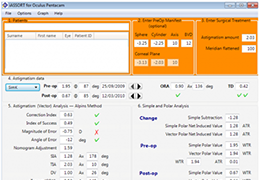

ANYTHINK 经导管主动脉瓣膜置换术分析系统